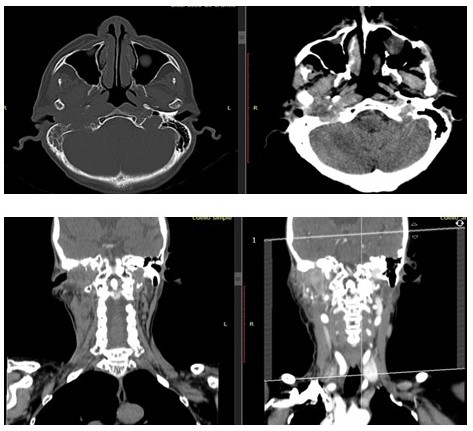

La paciente realiza TC controles de cráneo y cuello 18/03/2020 con cambios involutivos corticales y subcorticales y cambios posquirúrgicos a nivel de mastoides derecha, evidenciándose LOE adyacente a la misma y opacidad de las celdillas mastoideas derechas, sugiriendo RM para descartar recidiva o tumor residual (Figura 1). En dicho año no es posible recibir tratamiento con yodo radiactivo por lo que refieren a servicio de oncología médica, el cual tampoco logra canalizar por situación socioeconómica.

En TC de cuello simple (18/05/2021) de control, reporta hacia la región paralaringofaríngea derecha una imagen más o menos definida, sólida, de 10,2 cm x 13,8 cm en sus diámetros anteroposterior y transverso que se extiende discretamente hasta la luz de la orofaringe y que coexiste con irregularidad de la cortical de región occipital adyacente (Figura 3).